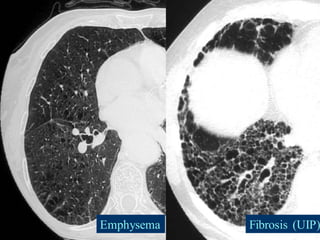

Combined Pulmonary Fibrosis and Emphysema

The combination of emphysema in the upper lobes and fibrosis in the

lower lobes (CPFE) is being increasingly recognized as a distinct entity in

smokers .

Patients are almost exclusively men in their 6th and 7th decades.

Lung volumes are relatively preserved despite markedly impaired diffusion

capacity and hypoxemia during exercise.

Honeycombing, reticular opacities, and traction bronchiectasis are the

most frequent findings at high-resolution CT in the lower lungs, while the

upper lungs exhibit paraseptal and centrilobular emphysema